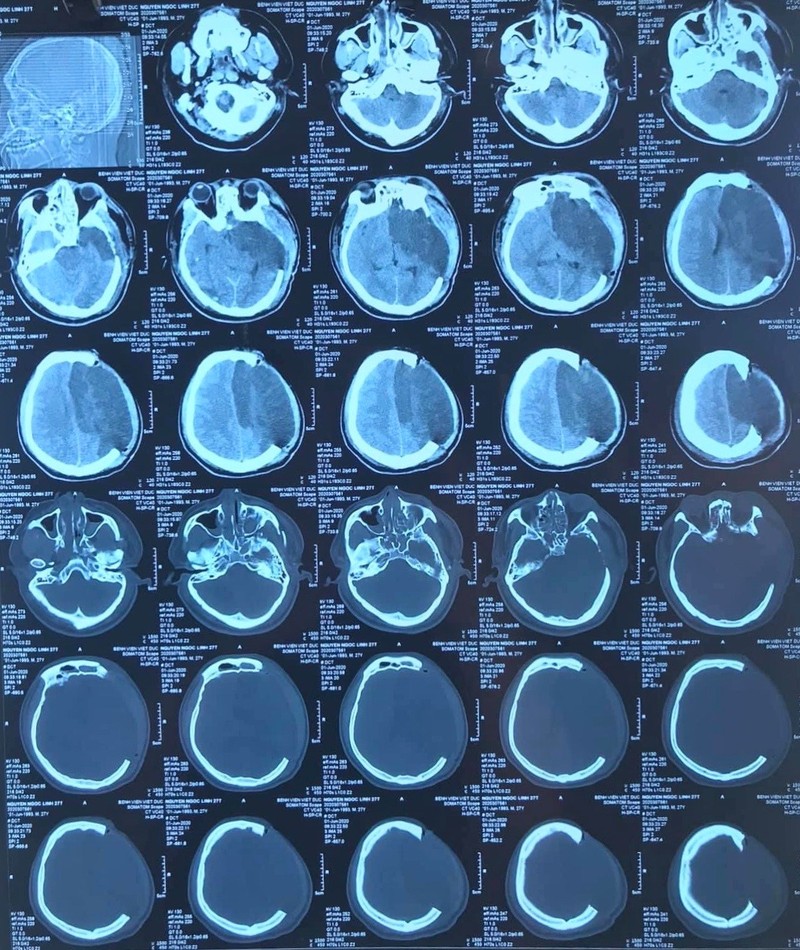

Các thiết bị y tế hiện đại được các bác sĩ sử dụng để hạ thân nhiệt chỉ huy cho bệnh nhân (Ảnh: BVCC)

TS. BS. Lưu Quang Thùy - Phó Giám đốc Trung tâm Gây mê và Hồi sức ngoại khoa, Bệnh viện Hữu nghị Việt Đức - cho biết: 3 phương pháp cuối cùng điều trị tăng ICP là gây mê bằng barbiturate, mở sọ giải áp hoặc hạ thân nhiệt chỉ huy (barbiturate coma, decompressive craniectomy or hypothermia). Bệnh nhân đã được an thần và mở sọ giải áp cũng không giảm được ICP, cuối cùng hạ thân nhiệt được ứng dụng để cứu sống bệnh nhân.

Trong năm 2016, tại hội nghị về hạ thân nhiệt tại Philadelphia - Mỹ, các báo cáo viên đã nói nhiều về vấn đề này, đến nay kỹ thuật này được ứng dụng tại Trung tâm Gây mê và Hồi sức ngoại khoa, Bệnh viện Hữu nghị Việt Đức, mang lại hiệu quả điều trị cao.